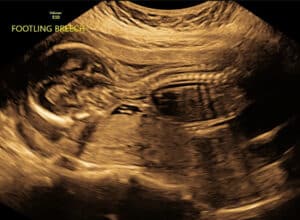

removing-fallopian-tube-bands-Sharps-Chapel-TNWe are so thankful and blessed to be pregnant with this sweet baby boy.

Monday we will officially reach “half baked” and be 20 weeks!